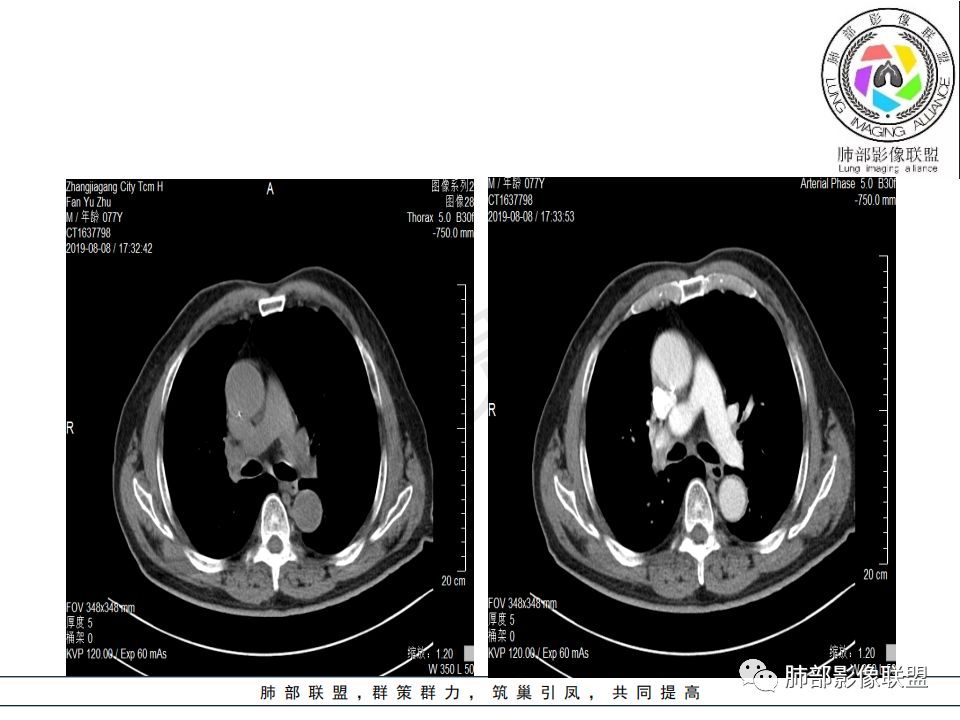

右肺主支气管有软组织肿块,向腔内外生长,右肺上叶肺不张,边缘光滑,增强扫描不均匀强化。考虑恶性肿瘤,鳞癌可能。

影像:影像右侧大支气管阻塞,临床没有症状或很轻微,要想到胃腺癌转移;胸壁代偿好,透亮度稍低不明显,慢性过程;34.8-52.5HU,主病灶支气管前壁另有1结节,都做成增强两期了,动脉期较平扫有强化;

晨读:患者老年男性,以咳嗽一月就诊,少量白痰,胸CT:纵隔右移,右肺体积缩小,气管下段管壁可见结节样改变,气管软骨变形,气管下段及右主支气管可见新生物向管壁浸润,并向管腔外生长,右上肺肺不张,但不张边缘可见病灶呈膨胀性生长,可见分叶,增强后强化明显。考虑:肺部恶性病变(鳞癌?)

右肺上叶肿块,边缘光滑,略膨隆,近段支气管堵塞,平扫密度均匀,增强后不均匀强化,其内可见不规则血管和坏死,纵隔淋巴结肿大,老年男性,无感染性病史,综合考虑恶性肿瘤(鳞癌,腺癌),鉴别:OP(一般下叶多见)